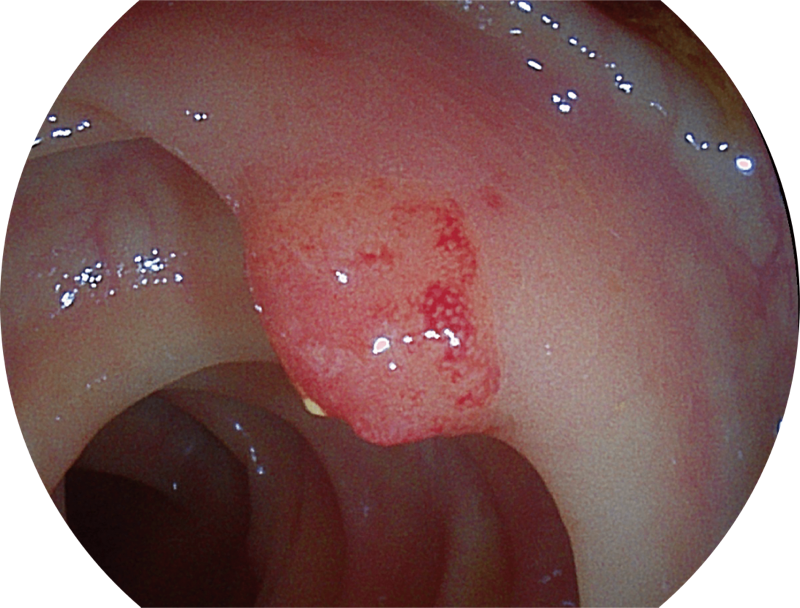

能够凸显黏膜浅层和中层血管轮廓,适用于中、远景观察下的病灶识别和早癌筛查。